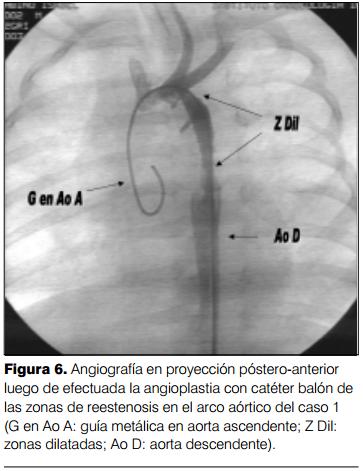

A la edad de 4 meses comienza con polipnea que va en aumento progresivo, comprobándose en el examen clínico los signos de recoartación de aorta. El ecocardiograma confirmó la presencia de recoartación significativa. Se traslada al ICI y se procede a efectuar cateterismo cardíaco que muestra un gradiente de 40 mmHg entre aorta ascendente y aorta descendente, con dos zonas de estenosis, una proximal y otra distal en el puente de vena cava superior izquierda, procediendo a efectuar angioplastia con catéter balón GHOST de 5 x 2 mm, quedando un gradiente residual de 10 mmHg con buena evolución posterior, persistiendo moderada hipertensión arterial pulmonar (en control con ecocardiograma doppler) en un paciente asintomático (figuras 4, 5,y 6).